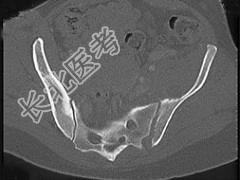

- 单项选择题男,56岁, 右髋部疼痛,结合图像, 最可能的诊断是 ( )

A、骶髂关节炎

B、骶髂关节结核

C、强直性脊柱炎

D、骨转移瘤

E、类风湿关节炎